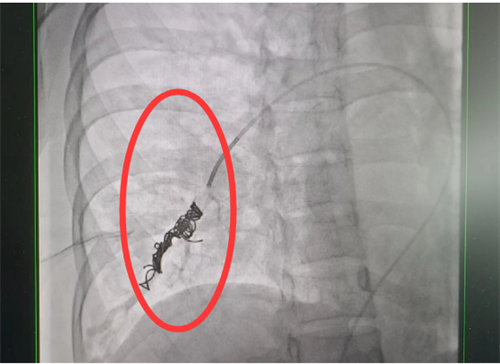

目前治疗肺动静脉瘘的方法有两种—介入手术及外科切除,可根据患者具体情况选择合适干预方式。通过积极处理,梁瑶脑梗症状得到控制,随后转入我院外周血管介入科进行介入手术治疗。此类手术难度大,风险高,经科室团队仔细讨论,定下最佳方案,为患者顺利实施了肺动静脉瘘封堵术,手术全程4小时,术后平稳回到病房。术后复查肺动静脉瘘已消失不见,经过后续的对症治疗和护理,梁瑶恢复良好,于5月上旬出院。

栓塞术后造影